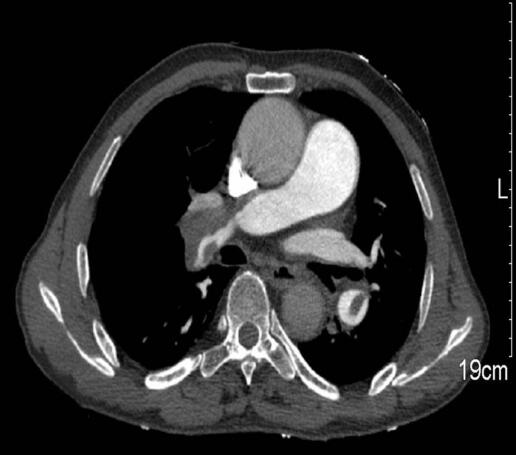

肺动脉CTA:双肺动脉干可见低密度充盈缺损,右上肺动脉未见显影,右下肺动脉、左下肺动脉可见低密度充盈缺损(图1,2)。双侧下肢静脉内可见广泛低密度充盈缺损。

图1

图2